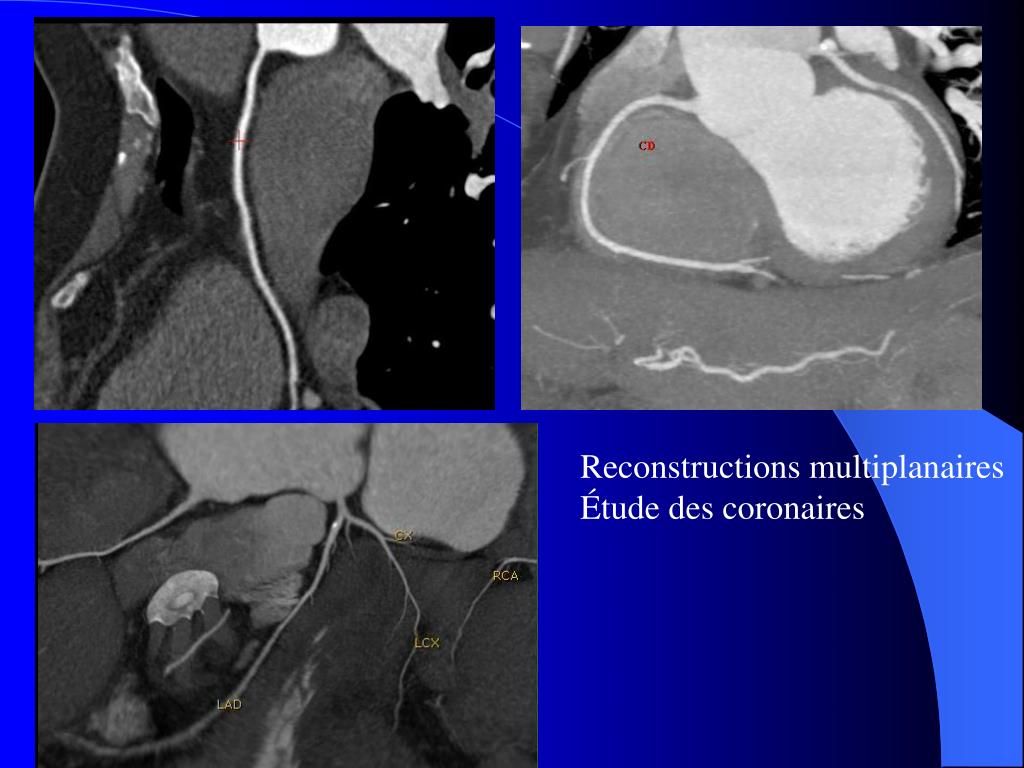

7. Reconstructions multiplanaires Étude des coronaires